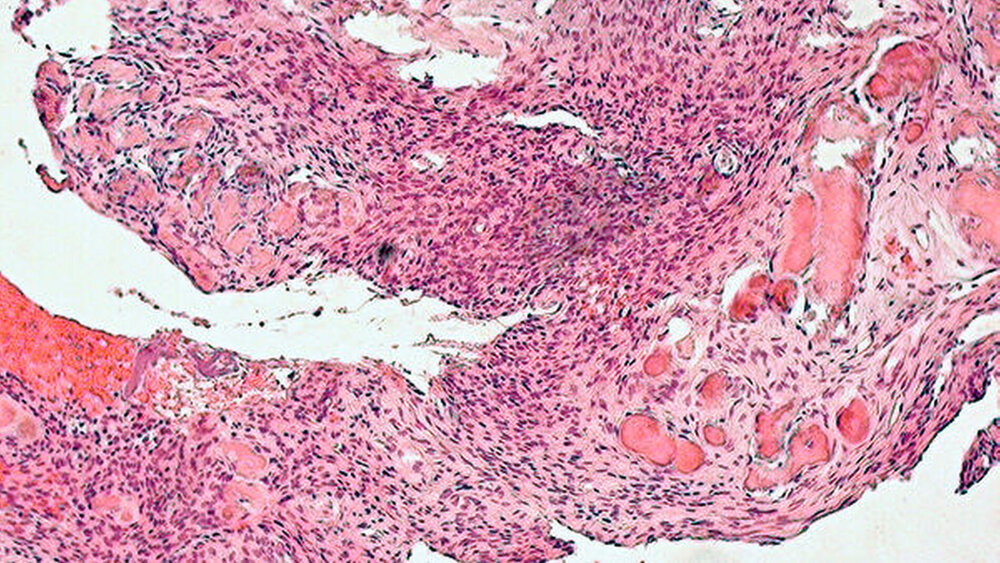

Die histopathologische Aufbereitung (Abbildung 5) ergab die Diagnose eines juvenilen psammomatoiden ossifizierenden Fibroms mit einem synchronen peripheren Riesenzellgranulom der darüber liegenden Schleimhaut. Parathormon, Calcium und Phosphat zeigten im Serum keine Auffälligkeiten, so dass ein Hyperparathyreoidismus ausgeschlossen werden konnte. Die angebotenen Nachsorgetermine wurden durch die Patientin in der Folge leider nicht wahrgenommen.

Das juvenile psammomatoide ossifizierende Fibrom ist durch ein fibroblastäres Stroma gekennzeichnet, in das kleine Ossikel, das heißt knöcherne Partikel, eingelagert sind. Mit eingelagert in das fibroblastäre Stroma sind vielkernige Riesenzellen, die auch als Charakteristikum des peripheren Riesenzellgranuloms angesehen werden und die ebenfalls durch die Pathologie diagnostiziert wurden.